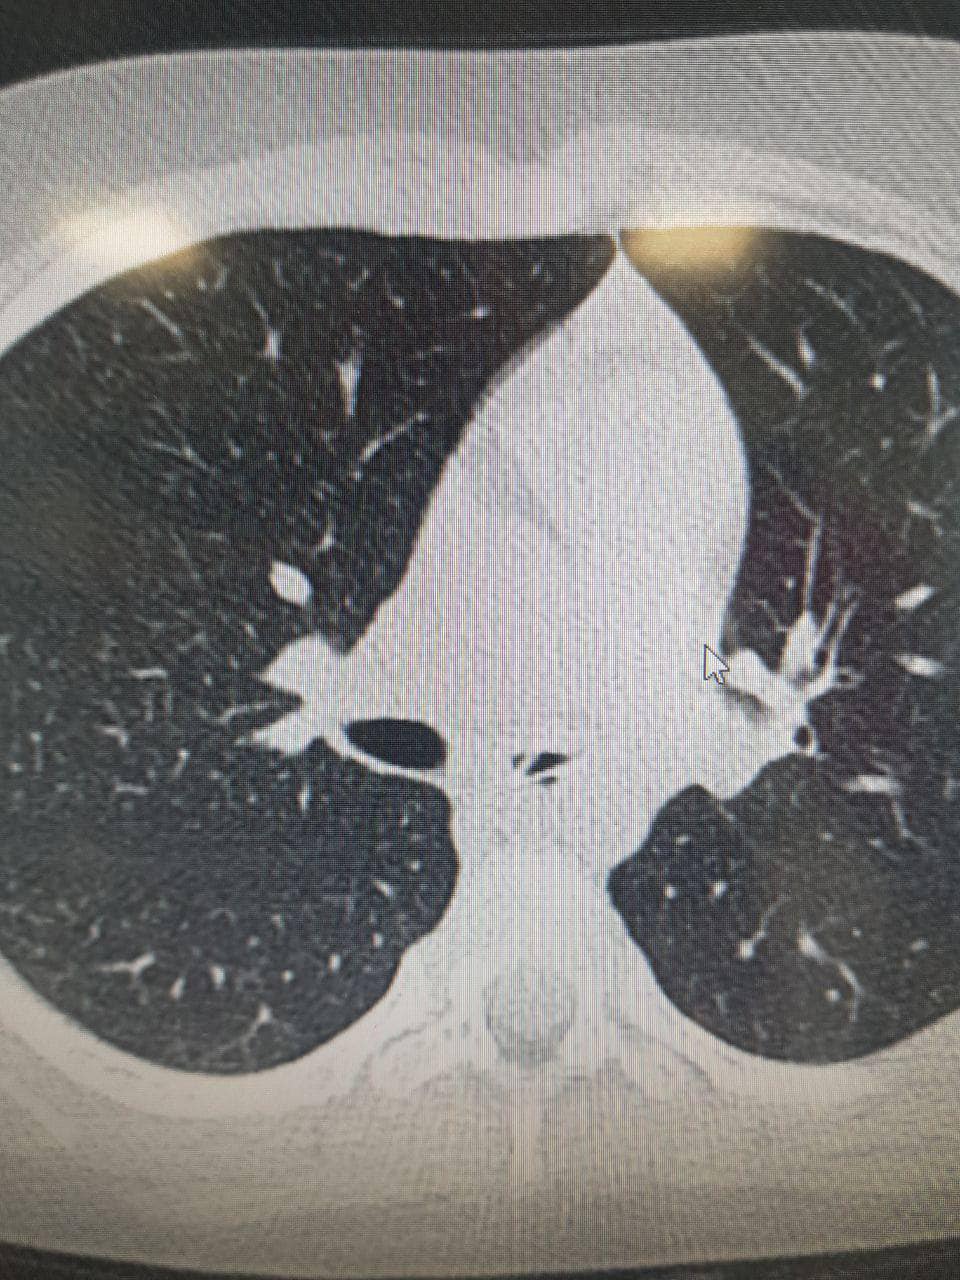

В Киеве врачи удалили игрушечную ложечку длиной 4 сантиметра с дыхательных путей 6-летней девочки. До этого ребенок в течение нескольких месяцев жаловался на кашель и затрудненное дыхание.

Там врачи во время обследовании обнаружили чужеродный предмет в дыхательных путях девочки. Позже оказалось, что этим предметом была пластиковая ложечка длиной в 4 сантиметра.

"Нетипичным было размещение ложечки в левом бронхе. Ведь почти всегда посторонние предметы попадают в правую сторону. Также удивило то, что девочке 6 лет - обычно подобные случаи случаются с детьми в возрасте до 3 лет", - рассказал Сергей Руденко, заведующий отделением педиатрии.